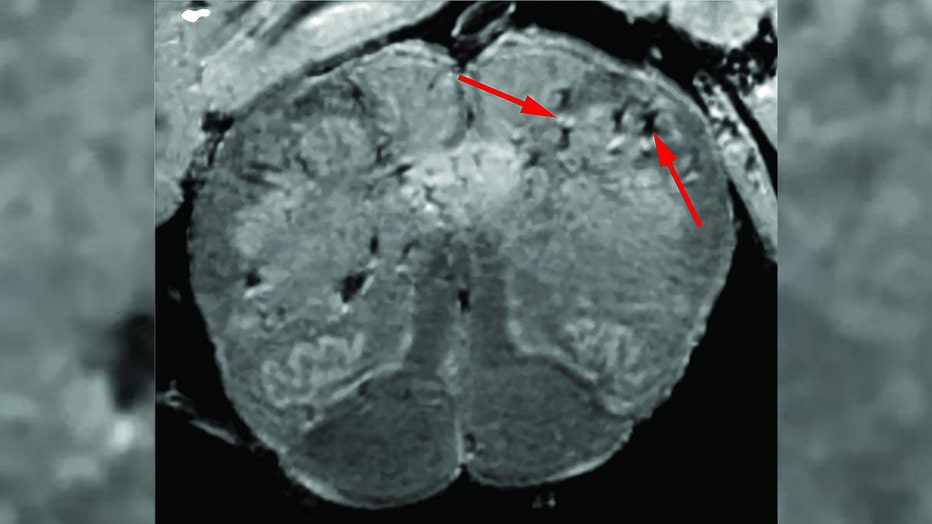

NIH researchers consistently found blood vessel damage in the brains of COVID-19 patients but no signs of SARS-CoV-2 infections. Arrows point to light and dark spots that are indicative of blood vessel damage observed in the study.